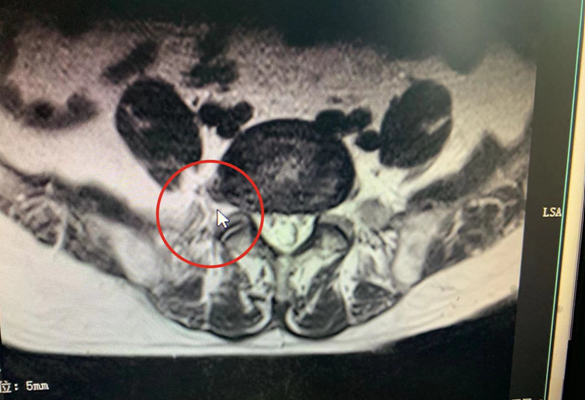

不堪其扰的王大爷来到珠海广安手足外科就诊,医院副院长邱庆明检查发现:王大爷第五腰椎至第一骶椎处的椎间盘突出非常严重,常人直腿抬高一般可达70度,但王大爷最高只能抬到40度。因为王大爷年纪较大,患病期间神经压迫导致睡眠不佳,长此以往会影响到身心健康,医患讨论后决定,立即给王大爷进行腰间椎盘摘除手术。在骨科医护团队数小时的通力合作下,王大爷的手术顺利完成。治疗一段时间后,王大爷不仅可以下地走动,心情也开朗不少,感觉非常满意。邱庆明